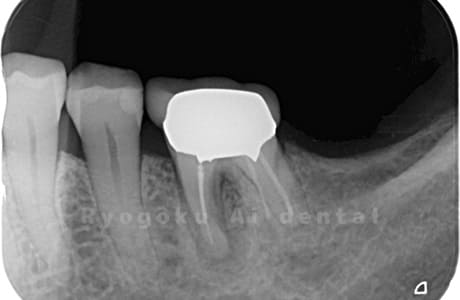

Case07

- 原因

- 右下6番歯根破折

-

- 治療内容

- インプラント治療

- 治療費用

- 約600,000円

右下の腫れが治らないとの事でご来院された患者様です。歯が割れていたため、抜歯を行い、骨に代わるお薬を入れ、インプラントを埋入致しました。経過良好で大変満足していただけました。

<リスク・副作用>

治療後、痛みや違和感、出血、腫れなどが出る事があります。喫煙者、糖尿病などの方の場合、歯が生着しない場合があります。